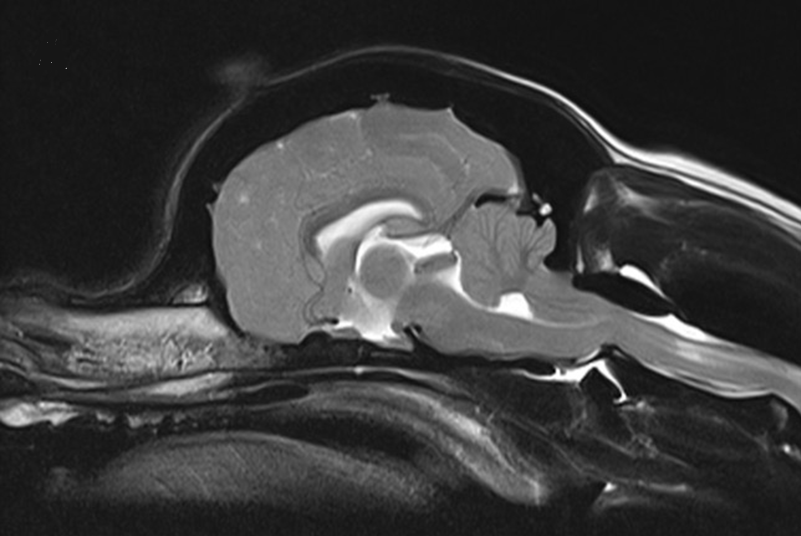

Syringohydromyelia in Cavalier King Charles spaniels. Rusbridge C, MacSweeny JE, Davies JV, Chandler K, Fitzmaurice SN, Dennis R, Cappello R, Wheeler SJ. J Am Anim Hosp Assoc. 2000 Jan-Feb;36(1):34-41.

Chiari 1/syringomyelia complex in a King Charles Spaniel. Churcher RK, Child G. Aust Vet J. 2000 Feb;78(2):92-5. Quote: "A 9-year-old King Charles Spaniel presented with a history of progressive forelimb weakness and paroxysmal involuntary flank scratching over a 2-year period. Neurological examination suggested a myelopathy of C1 to C4 spinal cord segments. Advanced imaging studies revealed hydrocephalus, caudal herniation of part of the caudal lobe of the cerebellum through the foramen magnum and marked syrinx formation to the level of the caudal thoracic spine, resembling Arnold-Chiari malformation with secondary hydromyelia in humans. Mechanical obstruction at the craniocervical junction, altering CSF flow dynamics, may lead to syrinx formation. Response to diuretic therapy was moderate but surgical decompression may offer better long term prognosis."

Neurological signs and results of magnetic resonance imaging in 40 cavalier King Charles spaniels with Chiari type 1-like malformations. Lu D, Lamb CR, Pfeiffer DU, Targett MP. Vet Rec. Aug 2003;153(9):260-3. Quote: In human beings a Chiari type 1 malformation is a developmental condition characterised by cerebellar herniation and syringohydromyelia. Abnormalities compatible with such a malformation were identified by magnetic resonance imaging in 39 cavalier King Charles spaniels with neurological signs and in one neurologically normal cavalier King Charles spaniel that was examined postmortem. The dogs with these abnormalities had a wide variety of neurological signs, but there was no apparent correlation between the neurological signs and the severity of cerebellar herniation, syringohydromyelia or hydrocephalus.

Chiari-like malformation and syringomyelia in normal cavalier King Charles spaniels: a multiple diagnostic imaging approach. J. Couturier, D. Rault, L. Cauzinille. J Small Anim. Pract. 2008 Sept; 49(9):438-443. Quote: "Results: Of the 16 [CKCS] dogs in the study, 7 had syringomyelia (43.7%). All dogs had cerebellar herniation, suggesting Chiari-like malformation and also a tendency to occipital dysplasia. Computed tomography measurements of the caudal fossa are reported. In one dog, a syrinx was identified by ultrasonography. The only difference between dogs with or without syringomyelia was that dogs with Chiari-like malformation/syringomyelia were statistically older. Clinical Significance: The incidence of Chiari-like malformation and syringomyelia may be high in an asymptomatic population of cavalier King Charles spaniel. Computed tomography measurements reported in this study should now be compared with those of a symptomatic population to evaluate the hypothesis that dogs with Chiari-like malformation/syringomyelia syndrome have a smaller caudal fossa. This study did not identify a smaller caudal fossa in an asymptomatic cavalier King Charles spaniel population with syringomyelia. Ultrasonography probably has a low sensitivity for diagnosis of Chiari-like malformation/syringomyelia."

Morphology of the Caudal Fossa in Cavalier King Charles Spaniels. Sofia Cerda-Gonzalez, Natasha J. Olby, Susan McCullough, Anthony P. Pease, Richard Broadstone, Jason A. Osborne. Vet. Radiology & Ultrasound, Jan/Feb 2009;50(1):37-46. Quote: "Chiari malformations and syringohydromyelia are an important disease complex in Cavalier King Charles Spaniels. Although abnormalities in caudal fossa morphology are considered major contributors to the development of this disease, limited information exists on the range of morphologies in Cavalier King Charles Spaniels and on the relationship of these to clinically evident disease. Sixty-four Cavalier King Charles Spaniels were studied. Each underwent a neurologic examination and magnetic resonance imaging of the cervical spine and brain. T2-weighted sagittal images were used to determine both the morphologic characteristics and volume of the caudal fossa in each dog. This volume was also analyzed as a percentage of total cranial cavity volume. Each attribute was correlated with neurological grade and presence of syringohydromyelia. Fifteen dogs had neurologic signs, and 59 had morphologic abnormalities of the craniocervical junction. While 27 dogs had syringohydromyelia, 13 of these were clinically normal. Cerebellar herniation and occipital dysplasia were common findings but were not associated with syringohydromyelia. Dorsal compressive lesions were noted at the first and second cervical vertebral junction. Factors associated with the presence of neurologic signs included syringohydromyelia and the ratio of caudal fossa/total cranial cavity volume; dogs with signs had significantly larger syringohydromyelia than asymptomatic dogs. Caudal fossa size was not associated with syringohydromyelia. A positive association was identified between foramen magnum size and length of cerebellar herniation. The prevalence of craniocervical junction abnormalities is high in Cavalier King Charles Spaniels. While several factors are associated with neurologic signs, occipital hypoplasia appears to be the most important factor."

Characteristics of Cerebrospinal Fluid Flow in Cavalier King Charles Spaniels Analyzed Using Phase Velocity Cine Magnetic Resonance Imaging. Sofia Cerda-Gonzalez, Natasha J. Olby, Richard Broadstone, Susan McCullough, Jason A. Osborne. Vet. Rad. & Ultrasound, Sep/Oct 2009, 50(5):467-476. Quote: "Syringomyelia is an important morbidity source in Cavalier King Charles Spaniels. Although abnormal cerebrospinal fluid (CSF) flow secondary to Chiari malformations is thought to cause syringomyelia in humans, this relationship is unknown in dogs. We used phase-contrast magnetic resonance (MR) imaging to evaluate CSF flow in dogs. Fifty-nine Cavalier King Charles Spaniels were assigned a neurologic grade reflecting their neurologic status. Five normal control dogs of other breeding were imaged for comparison. The presence of syringomyelia was noted from sagittal MR images. The pattern and velocity of CSF flow were assessed using phase-contrast cine MRI at the foramen magnum, C2-C3 disc space, and within syrinxes. Flow was measured most easily with the neck flexed to mimic standing. CSF flow velocity in the dorsal aspect of the subarachnoid space at the foramen magnum was significantly higher in control dogs than Cavalier King Charles Spaniels. Flow was obstructed at the foramen magnum in 41 of 59 Cavalier King Charles Spaniels. Turbulent flow and jets were associated with syringomyelia presence and severity, and CSF flow velocity at C2/3 dorsally was inversely related to the presence of syringomyelia. Peak dorsal subarachnoid space CSF flow velocity at the foramen magnum and C2-C3 were together highly predictive of syringomyelia. CSF flow can be assessed in dogs using phase-contrast cine MRI. Obstruction to flow at the foramen magnum is common in Cavalier King Charles Spaniels and CSF flow pattern and velocity are related to the presence of syringomyelia."

Anatomical Distribution of Syringomyelia in Cavalier King Charles Spaniel With Chiari.Like Malformation. S Loderstedt, L Benigni, K Chandler, C Lamb, C Rusbridge, HA Volk. 22nd ESVN Annual Symposium, Sept. 2009; J Vet Intern Med, Jan/Feb 2010;24(1):253. Quote: "The objective of this study was to evaluate the prevalence and anatomical distribution of syringomyelia (SM) in clinically-affected CKCS. It was hypothesised that (1) SM is not restricted to the cervical region of the spine, (2) the maximal syrinx diameter can occur anywhere along the spinal cord, (3) there is an association between cervical syrinx diameter and distribution and SM in other regions of the spinal cord. Thirty-seven CKCS with clinical evidence of SM were studied prospectively. Magnetic resonance (MR) imaging of the brain and the entire spinal cord of each dog were performed at 1.5 Tesla. ... SM was not limited to the cervical region. SM was present in the region of the C1-C4 vertebral bodies in all dogs (100%) however it often was not limited to that area being also found at C5- T1 in 31/37 (84%), T2-L2 in 29/37(78%) and L3-L6 in 21/37 (57%). Maximal SM diameter occurred at C1-C4 in 19/37 (51%) dogs, at C5- T1 in 2/37 (5%), at T2-L2 in 15/37 (41%) and at L3-L6 in 1/37(3%) dogs, respectively. There was no significant difference between the mean syrinx diameter at the region C1-C4, C5- T1 and T2-L2 but mean syrinx diameter was less in the region L3-L6. Mean syrinx diameter at C1-C4 was positively correlated with mean syrinx diameter at C5- T1, T2-L2 and L3-L6 respectively. Many CKCS with a cranial cervical syrinx also have a syrinx affecting more caudal regions of the spinal cord. Dogs with a large cranial cervical syrinx tend to also have a large syrinx more caudal. MR imaging restricted to the cervical region will underestimate the extent of the syrinx and the severity of the disease process in the majority of dogs."